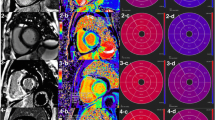

Predictive performance and clinical utility of radiomics models

Table 2 shows the predictive performance of the radiomics model for different sections. In the validation set, the AUC was 0.75, 0.77, 0.76, and 0.77 in the global LV, base, mid-ventricle, and apex, respectively (Fig. 2A). The DeLong test showed no statistical difference in AUC between different sections (all p > 0.05). Basal radiomics model was selected for further prognostic analysis.

ROC curve analysis for radiomics model of different sections in the validation set (A); ROC curves analysis for comparison of predictive performance of LV base-radiomics with semi-quantitative and quantitative LGE parameters (B); Rad-score for each patient in the training and validation sets (C); decision curve for the radiomics model in the training and validation sets (D)

The AUC of the basal Rad-score was higher than that of LGE total enhancement mass (0.77 vs. 0.54, p < 0.001) and LGE extent (0.77 vs. 0.53, p = 0.004) (Fig. 2B). Supplemental Table 2 shows the predictive performance of cardiac functional and LGE semi-quantitative and quantitative parameters in detail. The basal Rad-score of each patient in the training and validation sets is shown in Fig. 2C, which further confirms that radiomics can predict the adverse event of CA.

To estimate the clinical utility of established models, decision curve analysis (DCA) was performed by quantifying the net benefits at different threshold probabilities in the validation dataset and showed that both the training and validation sets to predict all-cause mortality had more benefit than either the “treat-all” model or the “treat-none” model (Fig. 2D).

Survival analysis and risk stratification

During a median follow-up duration of 12.9 months, a total of 40 CA patients died. Univariate survival analysis showed sex, age, diabetes, Mayo stage, QALE, LVEF, LVEDV, LVESV, and Rad-score were considered as factors for risk stratification of all-cause mortality in CA. ROC curves of the six factors with higher AUC are shown in Fig. 3A. Although the AUC of Mayo stage was higher than Rad-score, there was no statistically significant difference (0.81 vs. 0.77, p = 0.40). We further evaluated the predictive performance of Rad-score combined with Mayo stage and found that the AUC of their combination was higher than that of Mayo stage alone (0.86 vs. 0.81, p = 0.03) or Rad-score alone (0.86 vs. 0.77, p = 0.01), as shown in Fig. 3B. Other imaging indices such as EF, LGE semi-quantitative, and quantitative parameters combined with Mayo stage had no incremental value.

Survival of patients was stratified by the risk classification according to the Rad-score cut-off value of 0.66, which was the best predictor of survival (HR 8.91; 95% CI, 3.89–20.44; p < 0.001) (Fig. 4). The survival curve indicates that there is an approximately 84% chance of survival at 12 months in patients with the Rad-score < 0.66 compared with 33% for patients with Rad-score ≥ 0.66. Figure 5 shows the radiomics analysis and prognosis correlation from LGE images of three CA patients, which suggests that radiomics model is a better prognostic assessment for CA.